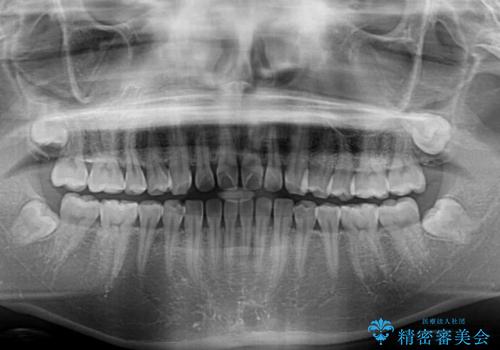

すきっ歯とオープンバイト インビザライン・ライトで改善

オープンバイトのため、奥歯に負担のかかる咬合状態であったので、矯正治療を提案したところ、希望をされました。

すきっ歯程度の軽度の歯列不正であったため、インビザライン・ライトにより咬合改善を行うこととしました。